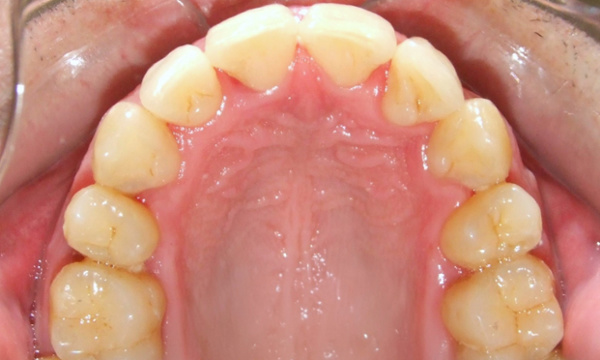

Not all orthodontic journeys start on the right path. This patient came to us with partial braces and a desire for clinical excellence. Dr. Martinez accepted the challenge, providing the expert, hands-on care necessary to "rescue" this complex case. After 24 months of specialized treatment in our Miami orthodontic practice, we achieved a healthy, stable, and properly aligned smile. Experience the difference 35 years of expertise makes.